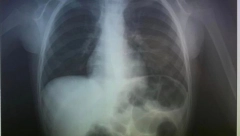

DEČAK PROGUTAO NOVČIĆ, GLEDAJTE GDE JE ZAVRŠIO Drama porodice na Kritu na dočeku

02.01.2024. 13:11